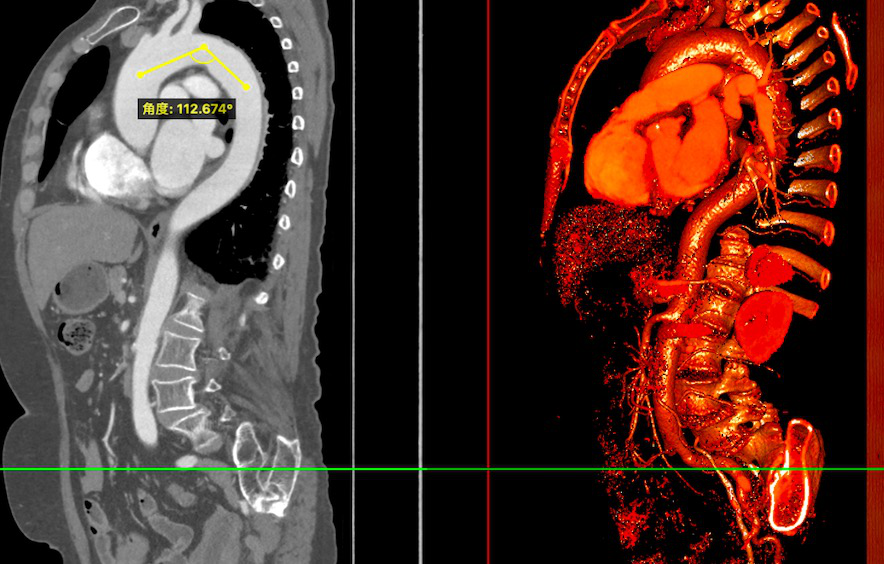

CT评估:

瓣环周长74.6mm,左室流出道周长79.4mm,左冠高度9mm(瓣叶长14mm),右冠高度10mm(瓣叶长11mm),窦宽31/29/30mm,STJ距瓣环高度14.5mm,最大直径约27.6mm。

纵切面

术前分析及手术策略:

患者三叶瓣,瓣叶增厚,右窦、无冠窦钙化严重,形态分布可能导致术后仍有轻度瓣周漏;右冠瓣瓣叶长,右冠开口处可见瓣叶且靠近瓣叶交界,且右窦钙化分布会将瓣膜往左侧推,结合ST-J高度和大小,冠脉风险较高,需22mm球囊预扩评估。

经团队评估,结合根部形态及病情等因素,决定选用VitaFlow Liberty™电动可回收瓣膜输送系统,22mm球囊预扩,预装TAV27瓣膜,体循干备。计划植入深度1-2mm。